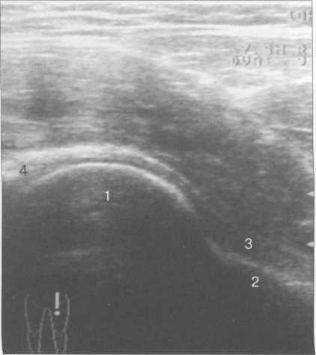

При сканировании из переднего доступа оценивают тазобедренный сустав и мягкие ткани паховой области, мышцы. Исследование сустава проходит продольным сканированием вдоль оси шейки бедра. Получают изображение переднего края крыши вертлужной впадины, вертлужной губы (хрящевого лимбуса, labrum acetabulare), которая дифференцируется как треугольная гиперэхогенная структура, а также передней поверхности головки бедренной кости, являющихся костными ориентирами. Отчетливо прослеживается тонкий суставной гипоэхогенный гиалиновый хрящ головки бедра (рис. 19.81). Собственно суставная капсула визуализируется вместе с волокнами преимущественно подвздошно-бедренной связки (рис. 19.82). Для определения отсутствия или наличия выпота в суставе измеряют расстояние между передней поверхностью шейки бедра и гиперэхогенной капсулой.

Рис. 19.81. УЗИ тазобедренных суставов взрослого.

1 — головка бедренной кости; 2 — шейка бедренной кости; 3 — капсула сустава и lig. iliofemorale; 4 — хрящевой (фиброзный) лимбус.